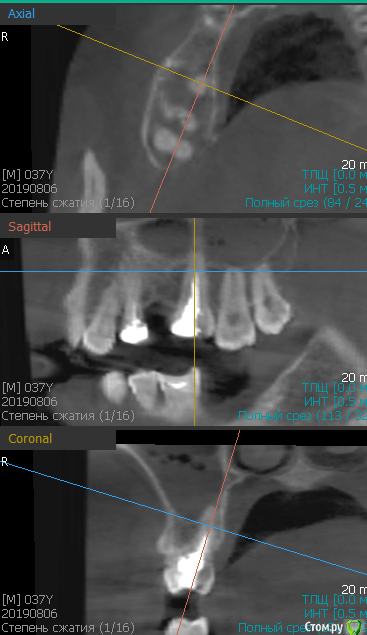

Сергей202020 Опубликовано 12 января, 2020 Поделиться Опубликовано 12 января, 2020 Добрый день. Прошу помощи. При очередном осмотре терапевтом была обнаружена киста на 4-ке с правой стороны так как 5-ки нет хотели ставить мост на 4-ку и 6-ку. Начали лечить сделали операцию, почистили, заложили лекарство,антибиотики. До операции присутствовала припухлость щеки с правой стороны где зуб, также чуть выше где то в районе 7-8 присутствует лимфоузел 2 сантиметра примерно, который уже лет 15-ть в одном и том же состоянии. Был у онколога говорит это липома. После удаления кисты и приема курса антибиотиков Цифран СТ почувствовал облегчение и по ощущениям щека перестала отекать. Контрольный снимок через 4 месяца показал что на 4-ке снова киста. Подождали 2 месяца сделали сннимок киста увеличилась. Сделали повторно ретроградную операцию так вроде сказали. Через пару месяцев началась боль при хотьбе, при перемешении головы, обратился к хирургу сделали снимок все хорошо сказала ничего не вижу иди с лору. Лор снимок гайморит, лечили сложными каплями и риностоп. После сложных капель боль отступила на второй, третий день...Но через какое то время боль опять нарастает...хорошо помогает омепразол...быстро снимает боль. Прошло пол года пришел на контроль, рассказал что боль при хотьбе на пятку, при постукивании по лицу, при перемещении головы. Боль локализуеться где то в районе 4-5-6 или пазухи не понять. При накусывании боли нет. Поставили мост на 4 и 6-ку. Перед установкой моста настоял сделать МРТ, хирург сказал что в гайморовой пазухе жидкость, наверное гайморит у 4-ки небольшое разряжение можно ставить мост. Вот 4-ме месяца снова мучаюсь.боль может быть неделю...потом проходит..нос залечил так что дышит правая ноздря лучше левой. Но боль не уходит. Замучался да и лимфоузел беспокоит еще есть с этой же стороны в шейном отделе со спины тоже лимфоузел где то 3*3, онколог говорит киста ищи нейрохирурга. Чувствую себя хорошо беспокоит только боль даже когда берусь за лицо за губы тоже присутствует тупая обширная боль... и припухлость щеки. Посмотрите пожалуйста МРТ..Страшно пропустить что то хуже, разряженности зуба)). Мне 38 лет. проживаю г.Воронеж. Спасибо огромное кто что то подскажет что делать. Ссылка на яндекс диск с CD диска файлы 333 мегабайта. Измучился, лор говоорит иди к стоматологу, стоматолог к лору, по лимфоузлам первый раз в онкодиспансере сказали лимфоузлы делали узи...второй раз липома и киста...при ощупывании руками)) измучился в край...Тот лимфоузел который в шеке 2 сантиметра два раза пытались взять что там...прокалывали но ничего не набираеться...только чешуйки плоского эпителя...Квест... ССЫЛКА https://yadi.sk/d/SO2MBUMZp53duQСпасайте...Спасибо всем... Ссылка на комментарий

___49___ Опубликовано 12 января, 2020 Поделиться Опубликовано 12 января, 2020 рассказал что боль при хотьбе на пятку, при постукивании по лицу, при перемещении головы. Боль локализуеться где то в районе 4-5-6 или пазухи не понять - клинически типичное проявление для патологического процесса в пазухе(гайморит например), а судя по снимку 6ка поддерживает данный процесс, лечение лекарствами будут лишь переводить процесс в ремиссию , но любое снижение иммунитета , простуда и т.п. возобновят всю симптоматику. Требуется работа в тандеме стоматолога и лор врача . Ссылка на комментарий